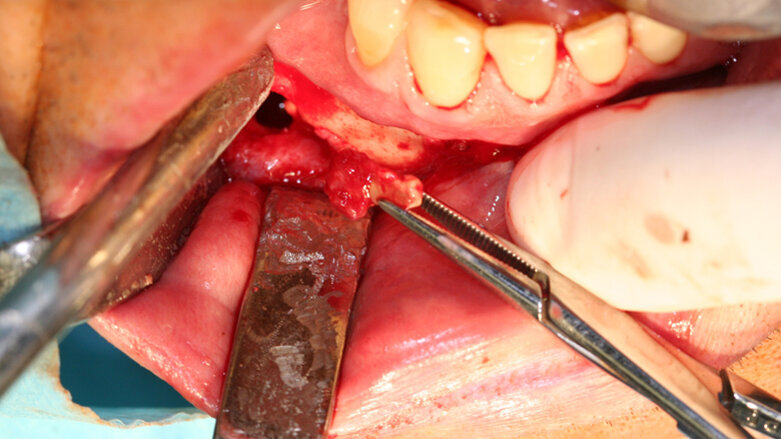

Při výkonech dentoalveolární chirurgie používáme koncovky osteoplastické, jejichž pomocí lze šetrně odpreparovat kostní tkáň nad retinovanými zuby ať v případě jejich následující extrakce nebo v případě následné fenestrace či tunelizace, kdy je možné jejich následné ortodontické zařazení do zubního oblouku.

Opatrnost doporučujeme při preparaci v blízkosti skloviny – pokud totiž dojde k přímému kontaktu piezochirurgické koncovky se sklovinou zubu, nelze vyloučit rozvoj mikrofraktur skloviny, která má odlišné mechanické vlastnosti než kost.

Osteotomické koncovky používáme pouze k separaci zubních tkání, které budeme závěrem extrahovat. S výhodou pro situace, kdy plánujeme okamžitou implantaci, je provedení extrakce pomocí piezochirurgie, ne však způsobem, který je často demonstrován na různých školeních a workshopech. Tam bývá stomatologům často doporučováno použití extrakční koncovky místo periotomu. To může vést k přehřátí okolní kosti a následným komplikacím ve smyslu alveolitis sicca. Extrakce v těchto situacích by měla být provedena jako postupná separace kořene a jeho odstranění po částech, přičemž okolní kostní tkáně se snažíme dotýkat minimálně, abychom nepoškodili kostní buňky zubního lůžka.